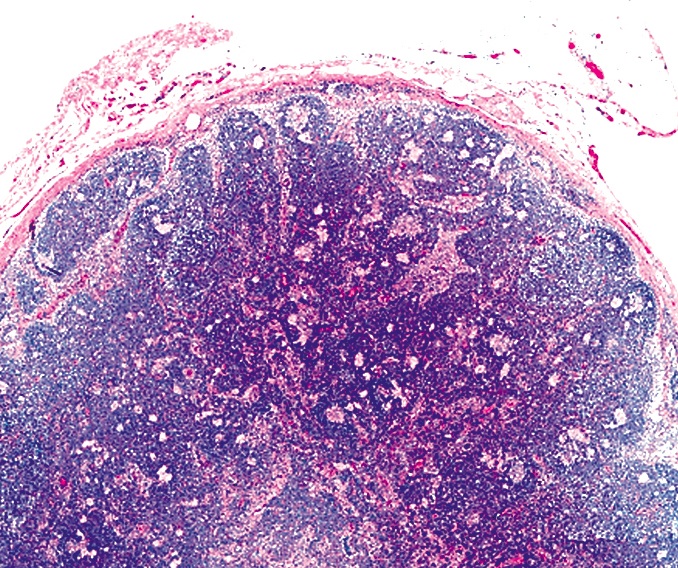

Microscopic (histologic) description

- Nodes show partial / complete effacement by storiform pattern of bland spindle cells, some with vacuoles

- Numerous vessels lined by plump endothelial cells, plasma cells and lymphocytes

- No multinucleated tumor cells, no foamy histiocytes

Microscopic (histologic) images

Contributed by AFIP and Chunyu Cai, M.D., Ph.D. (Case #532)

Cytology description

- Spindle cell proliferation resembling Kaposi sarcoma; no foamy histiocytes (Acta Cytol 1995;39:125)